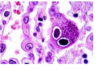

מהו הממצא

A

פטריית עובש- מוקור